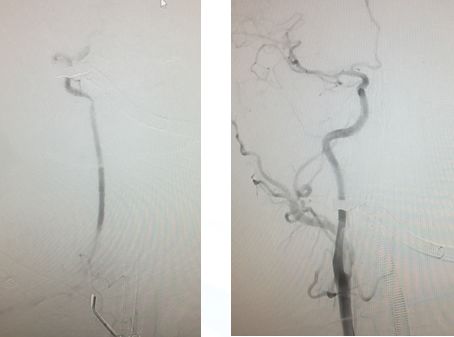

造影右侧椎动脉闭塞,右侧颈总动脉

左侧颈总、左侧椎动脉

左锥造影V4段先天性病变(狭窄?)

右椎入路微导管手推造影,寻找血管闭塞位置

右椎V4段狭窄,2.5*15球囊扩张(应用替罗非班)

13:40:应用3.0*13Apollo支架释放血管再通